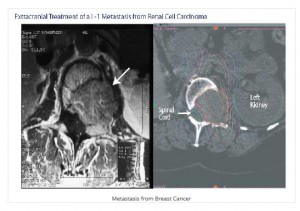

Σε γενικές γραμμές, σε ασθενείς με προσδόκιμο ζωής >6μηνων και με ελεγμένη την εξωκρανια νόσο, οι μονήρεις μεταστάσεις αντιμετωπίζονται είτε με χειρουργική επέμβαση είτε με στερεοτακτική ακτινοχειρουργική. Σε ασθενείς με 1-3 δευτεροπαθείς εγκεφαλικές εντοπίσεις επιλέγουμε την ακτινοχειρουργική.

Η χειρουργική επέμβαση αποτελει θεραπεία εκλογής κυρίως σε συμπτωματικές ευμεγέθεις εστίες για άμεση αποκατάσταση των νευρολογικών συμπτωμάτων ή και για την ιστολογική ταυτοποίηση της νόσου.

Σε μονήρεις ή και σε περισσότερες της μίας εγκεφαλικές μεταστάσεις ή/και που εντοπίζονται σε χειρουργικά δυσπρόσιτες περιοχές, το CyberKnife® αποτελεί μέθοδο πρώτης επιλογής αφού η χειρουργική αφαίρεση αυτών είναι δύσκολη έως αδύνατη.

Για τους ασθενείς που έχουν παρουσιάσει εγκεφαλικές μεταστάσεις το CyberKnife® είναι μία επιλογή εύκολη, ανώδυνη, αναίμακτη και ολοκληρώνεται συνήθως σε μία μόνο συνεδρία. Γι αυτό και έχει αποδειχθεί η προσφορότερη επιλογή για τον ασθενή και τον θεράποντα ιατρό του στις περιπτώσεις των εγκεφαλικών μεταστάσεων.